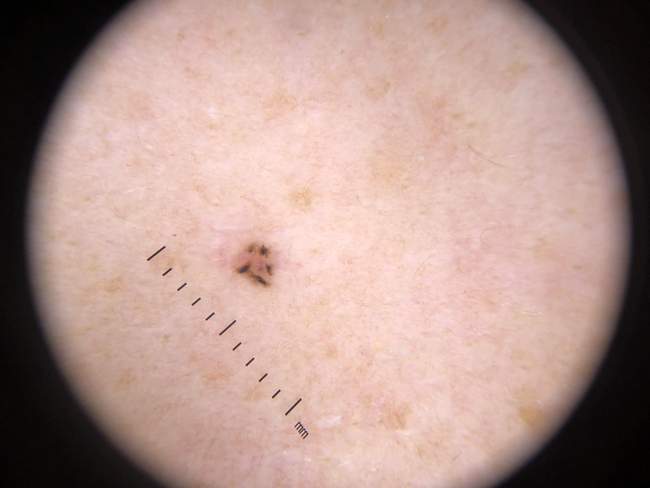

Dermatoskopia w diagnostyce BCC – cechy charakterystyczne

Dermatoskopia to badanie skóry pod powiększeniem 10-20x za pomocą specjalnego urządzenia – dermatoskopu. Metoda ta zwiększa dokładność rozpoznania BCC o 20-30% w porównaniu do oceny gołym okiem.

Charakterystyczne cechy dermatoskopowe BCC:

• Struktury liściaste (leaf-like areas) – brązowo-szare owalne struktury przypominające liście, układające się promieniście

• Gniazda barwnikowe (ovoid nests) – owalne, brązowe gniazda barwnikowe w obrębie zmiany

• Teleangiektazje arboryzujące – rozgałęzione naczynia krwionośne przypominające gałęzie drzewa (najczęstszy objaw – występuje w 80-90% BCC)

• Obszary sine-niebieskawe (blue-grey areas) – nagromadzenie melaniny w głębszych warstwach skóry

• Brak sieci barwnikowej – kluczowa cecha odróżniająca BCC od czerniaka (czerniak ma sieć barwnikową)

Czułość dermatoskopii w rozpoznaniu BCC wynosi 85-95%, a swoistość 80-90% według badań ESMO i AAD. Nowoczesne centrum diagnostyczne, takie jak Twoje Znamiona, używa wideodermatoskopii – zaawansowanej formy dermatoskopii z archiwizacją obrazów i możliwością porównania zmian w czasie.